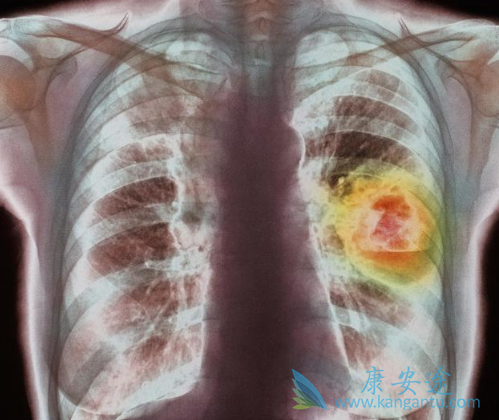

相信很多肺癌患者都治疗靶向药物吉非替尼(GEFITINIB),它是晚期肺癌的一线用药,能显著延长患者的生存时间和提高生活质量,但是仍有不少患者对吉非替尼仍有误解,其中主要表现在两个方面:一是吉非替尼的有效率与副作用大小相关;而是吸烟的患者不能服用吉非替尼?下边小编就这两大误区为大家好好澄清下。